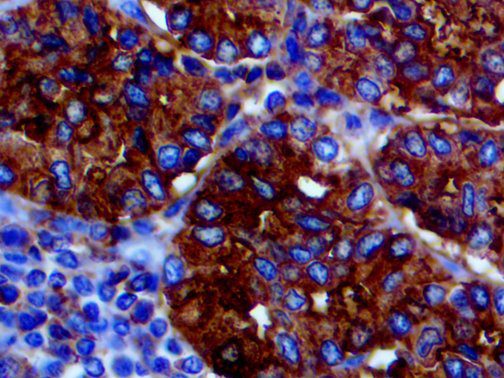

It is the ICU physician who is most likely to witness one of the deadliest manifestations of the abnormal immunological response, the cytokine storm syndrome (CSS). This response is also referred to by some as the cytokine release syndrome (CRS). CSS is characterized by continuous activation and expansion of macrophage and lymphocyte populations, which secrete large amounts of cytokines, causing the cytokine storm. This massive cytokine release is akin to hemophagocytic lymphohistiocytosis (HLH) disease, a syndrome characterized by initial unchecked and persistent activation of cytotoxic T lymphocytes and NK cells.

Clinical and laboratory manifestations of HLH include fever, enlarged liver and/or spleen, neurologic dysfunction, coagulopathy, liver dysfunction, cytopenias (i.e., low levels of erythrocytes, leukocytes, and/or platelets), hypertriglyceridemia, hyperferritinemia, hemophagocytosis, and eventually diminished NK cell activity as the immune system becomes progressively paralyzed. HLH can be familial (primary HLH) or secondary to another disease process (sHLH), such as rheumatic disease, in which it is referred to as macrophage activation syndrome (MAS, characterized by elevated ferritin).